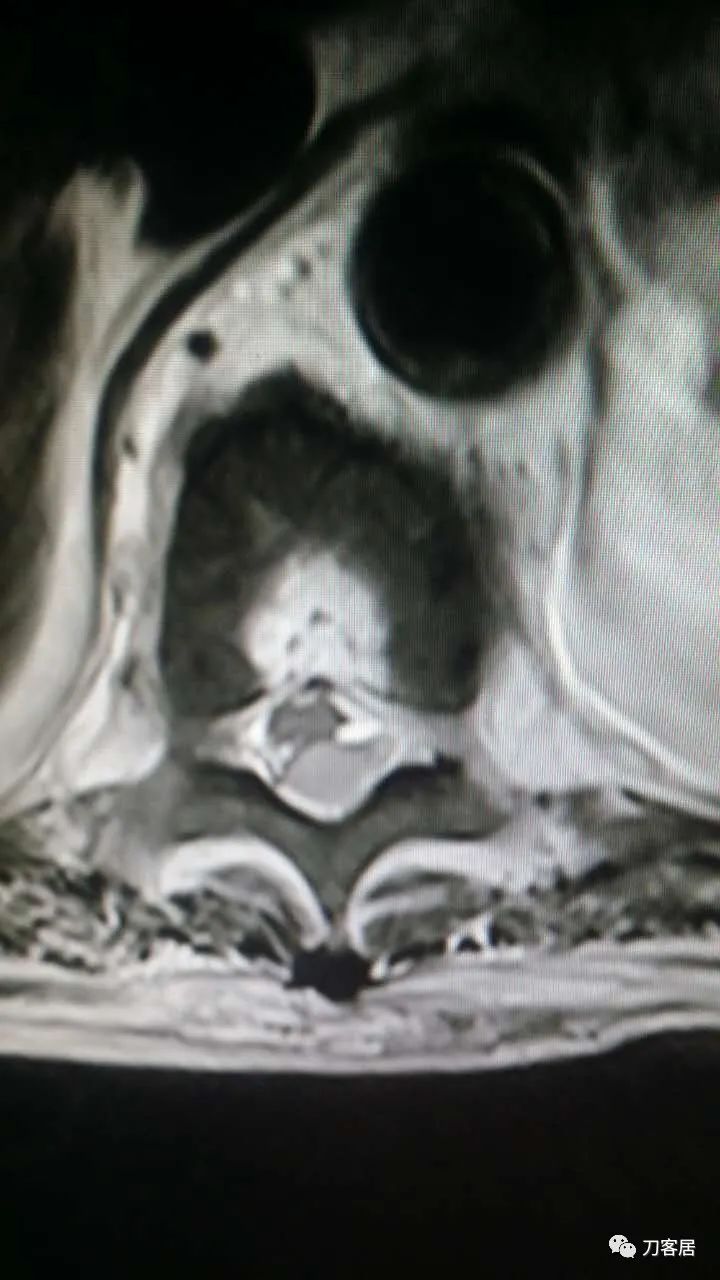

加注图14. 胸9-10椎管内后方高信号占位病变,考虑血肿形成。

加注图15. 胸9-10椎管内后方高信号占位病变,考虑血肿形成。

加注图16. 胸9-10椎管内后方高信号占位病变,考虑血肿形成。

加注图17. 胸9-10椎管内后方高信号占位病变,考虑血肿形成。